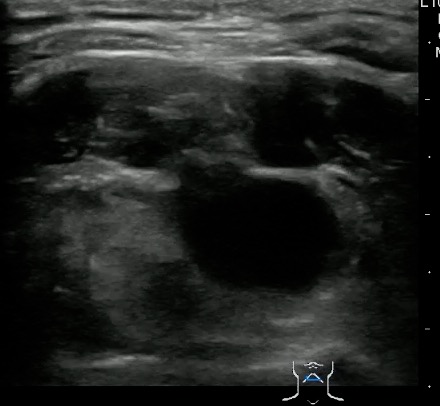

Thyroglossal duct cyst26

- Thyroglossal duct cysts typically related to hyoid bone:

- Often midline

- 25%-suprahyoid-submental region

- 75%-Infrahyoid or at the level of hyoid

- Variable sonographic appearance:

- Well-circumscribed anechoic cyst

- Increased through transmission

- Hypoechoic with internal debris

- No internal vascularity

- Heterogeneous pattern seen in repeated infections and hemorrhage due to prior aspirations

- Pseudo-solid echogenic appearance from proteinaceous contents secreted by epithelial lining

- Figure 34 and 35. Thyroglossal Duct Cyst

Video 22. Thyroglossal Duct Cyst